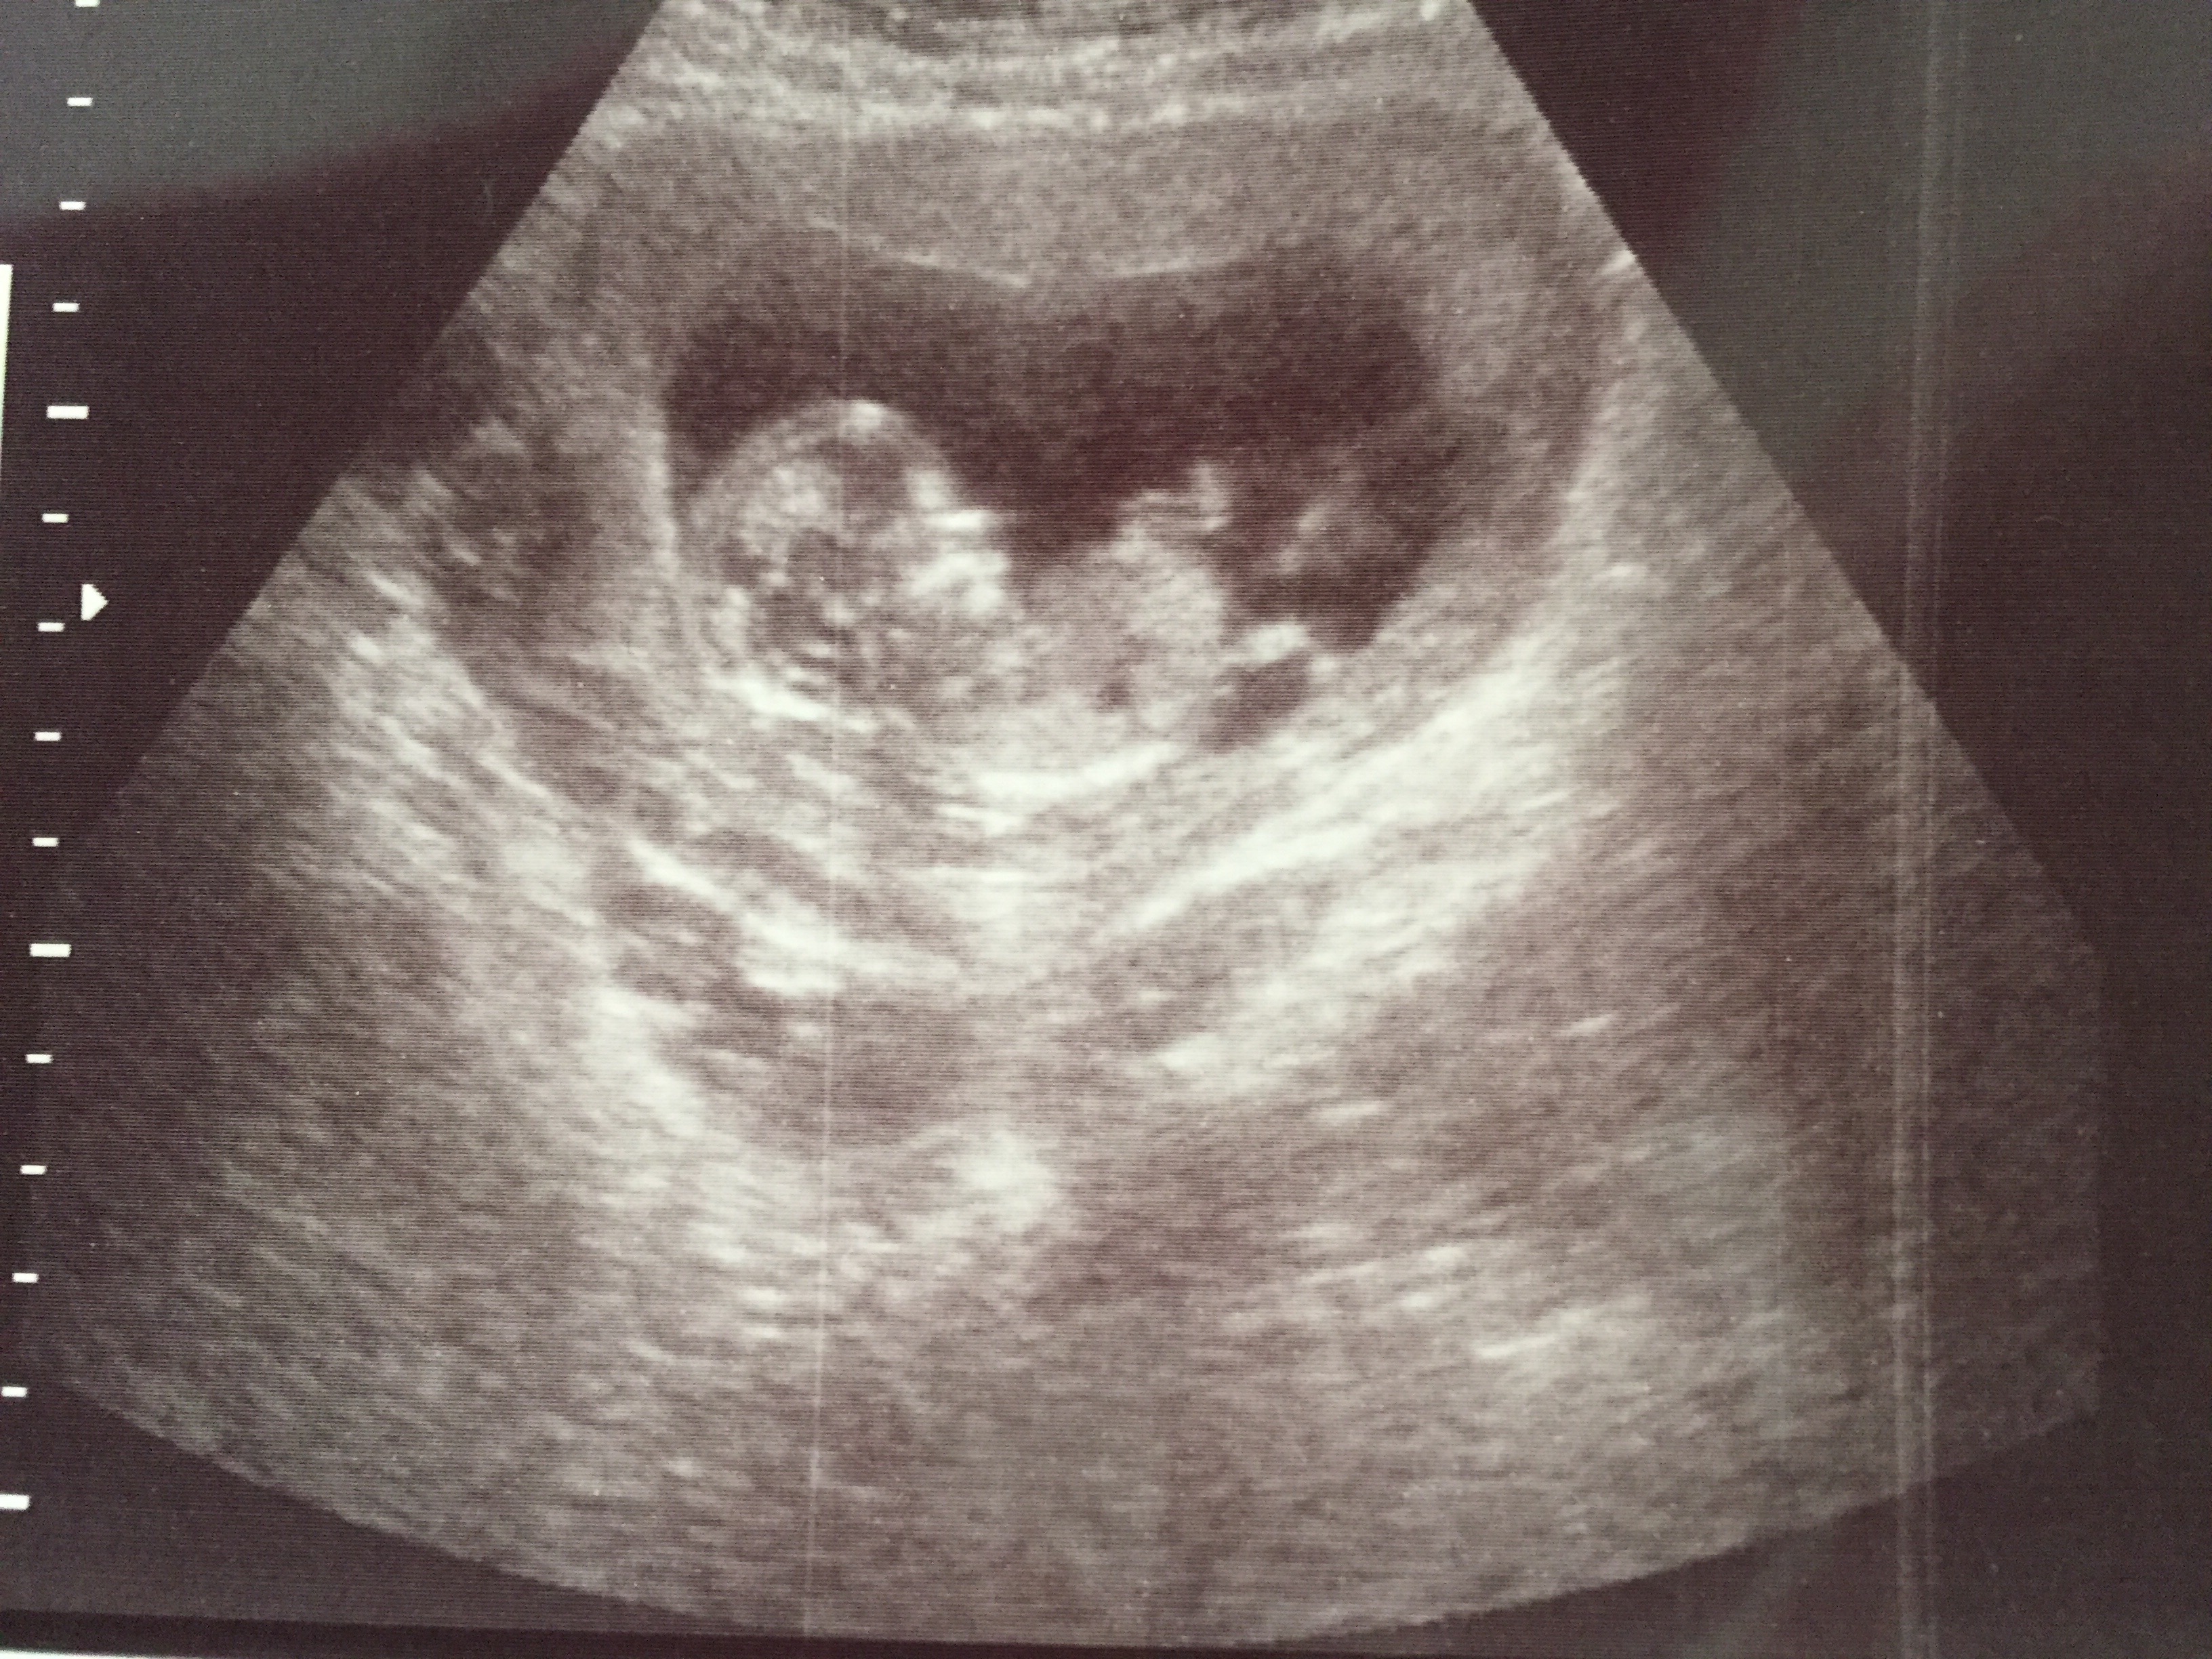

Told Boy at 13 weeks & told Girl at 16 weeks

went to an elective ultrasound at 13/14 weeks and was told boy but the Cord was between the legs and what she said was to be a "penis" seems way too long and it is also divided like a girl part. I have two boys already and their ultrasounds look completely different. After going to the elective ultrasound I saw my doctor at 16 weeksinformed us it was a girl and based off of the earlier ultrasound he gave us it looks girl also. Both my boys at 12 weeks were clear as day and this time my 13 week ultrasound from doctor had nothing between the legs.

I think the elective u/s gave us the wrong determination. Could this be a girl with swollen parts or cord over the girl parts? Attachment 28204Attachment 28205Attachment 28206Attachment 28207Attachment 28208